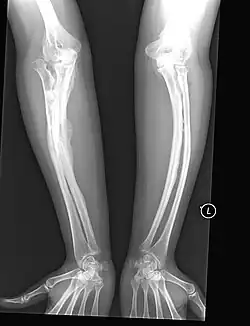

Osteogenesis imperfecta (IPA: /ˌɒstioʊˈdʒɛnəsɪs ˌɪmpɜːrˈfɛktə/;[4] OI), colloquially known as brittle bone disease, is a group of genetic disorders that all result in bones that break easily.[1]: 85 [9] The range of symptoms—on the skeleton as well as on the body's other organs—may be mild to severe.[5]: 1512 Symptoms found in various types of OI include whites of the eye (sclerae) that are blue instead, short stature, loose joints, hearing loss, breathing problems[10] and problems with the teeth (dentinogenesis imperfecta).[5] Potentially life-threatening complications, all of which become more common in more severe OI, include: tearing (dissection) of the major arteries, such as the aorta;[1]: 333 [11] pulmonary valve insufficiency secondary to distortion of the ribcage;[1]: 335–341 [12] and basilar invagination.[13]: 106–107

The main symptom of osteogenesis imperfecta is fragile, low mineral density bones; all types of OI have some bone involvement.[5] In moderate and especially severe OI, the long bones may be bowed, sometimes extremely so.[28] The weakness of the bones causes them to fracture easily—a study at the Endocrine Unit at the National Institute of Child Health in Karachi, Pakistan found an average of 5.8 fractures per year in untreated children.[29] Fractures typically occur much less after puberty, but begin to increase again in women after menopause and in men between the ages of 60 and 80.[1]: 486

OI type III causes osteopenic bones that fracture very easily, sometimes even in utero, often leading to hundreds of fractures during a lifetime;[24] early scoliosis that progresses until puberty; dwarfism (a final adult height frequently less than 4 feet or 120 centimetres); loose joints; and possible respiratory problems due to low rib cage volume causing low lung volumes.[5]: 1512

Diagnosis is typically based on medical imaging, including plain X-rays, and symptoms. In severe OI, signs on medical imaging include abnormalities in all extremities and the spine.[97] As X-rays are often insensitive to the comparatively smaller bone density loss associated with type I OI, DEXA scans may be needed.[5]: 1514

An OI diagnosis can be confirmed through DNA or collagen protein analysis, but in many cases, the occurrence of bone fractures with little trauma and the presence of other clinical features such as blue sclerae are sufficient for a diagnosis. A skin biopsy can be performed to determine the structure and quantity of type I collagen. While DNA testing can confirm the diagnosis, it cannot absolutely exclude it because not all mutations causing OI are yet known and/or tested for.[83]: 491–492 OI type II is often diagnosed by ultrasound during pregnancy, where already multiple fractures and other characteristic features may be visible. Relative to control, OI cortical bone shows increased porosity, canal diameter, and connectivity in micro-computed tomography.[98] OI can also be detected before birth by using an in vitro genetic testing technique such as amniocentresis.[99]